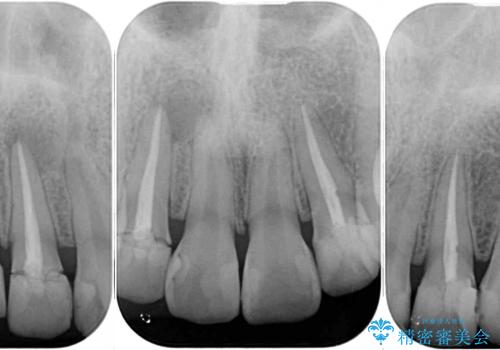

必要に応じて根管治療を行い、前歯6歯をオールセラミッククラウンで補綴することとしました。